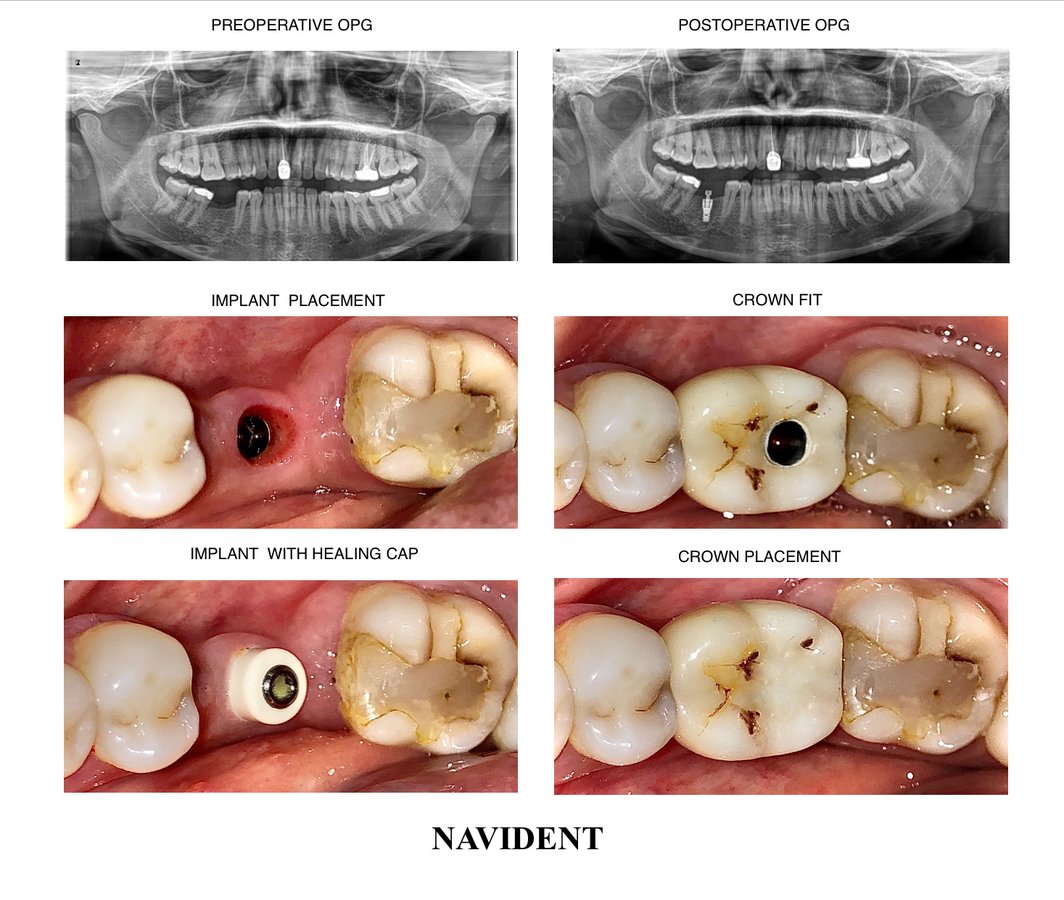

About Raga Dental Center for Dental Implants & Laser Raga Dental is a well established facility with experienced team of doctors , state of the art equipments and especially renowned for Implantology and waterlase Laser Dentistry. We are well equipped with Waterlase Laser, Navident for Navigation implant surgeries, 3D printer for Guided implant surgeries, Phillips zoom whitening for esthetic rehabilitation. We also excel in other ... (Show more)